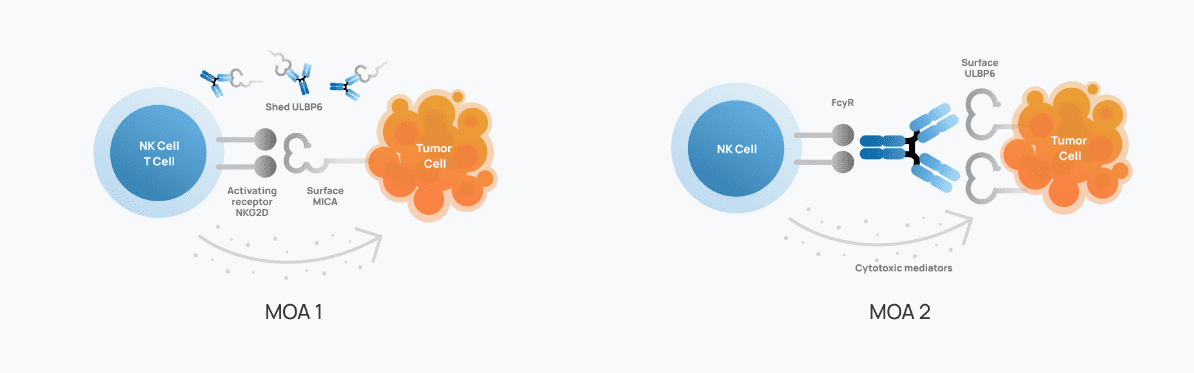

23andMe Scores FDA Clearance for Novel Cancer Immunotherapy Targeting NK Cells

– 23andMe Holding Co. (Nasdaq: ME), a genetics and biopharmaceutical company, announced The U.S. Food and Drug Administration (FDA) has cleared the investigational new drug (IND) application for 23ME-01473 (referred to…